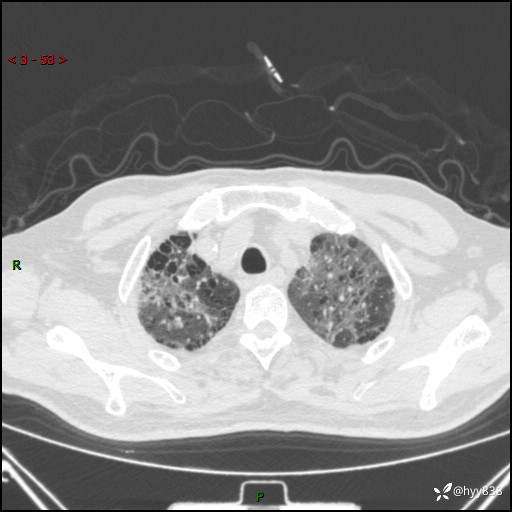

患者性别:男

患者年龄:64岁

简要病史:肝内胆管癌综合治疗后2周余,咳嗽、发热,咳白色泡沫痰。

辅助检查:CT

临床诊断:感染?

讨论:病变性质?